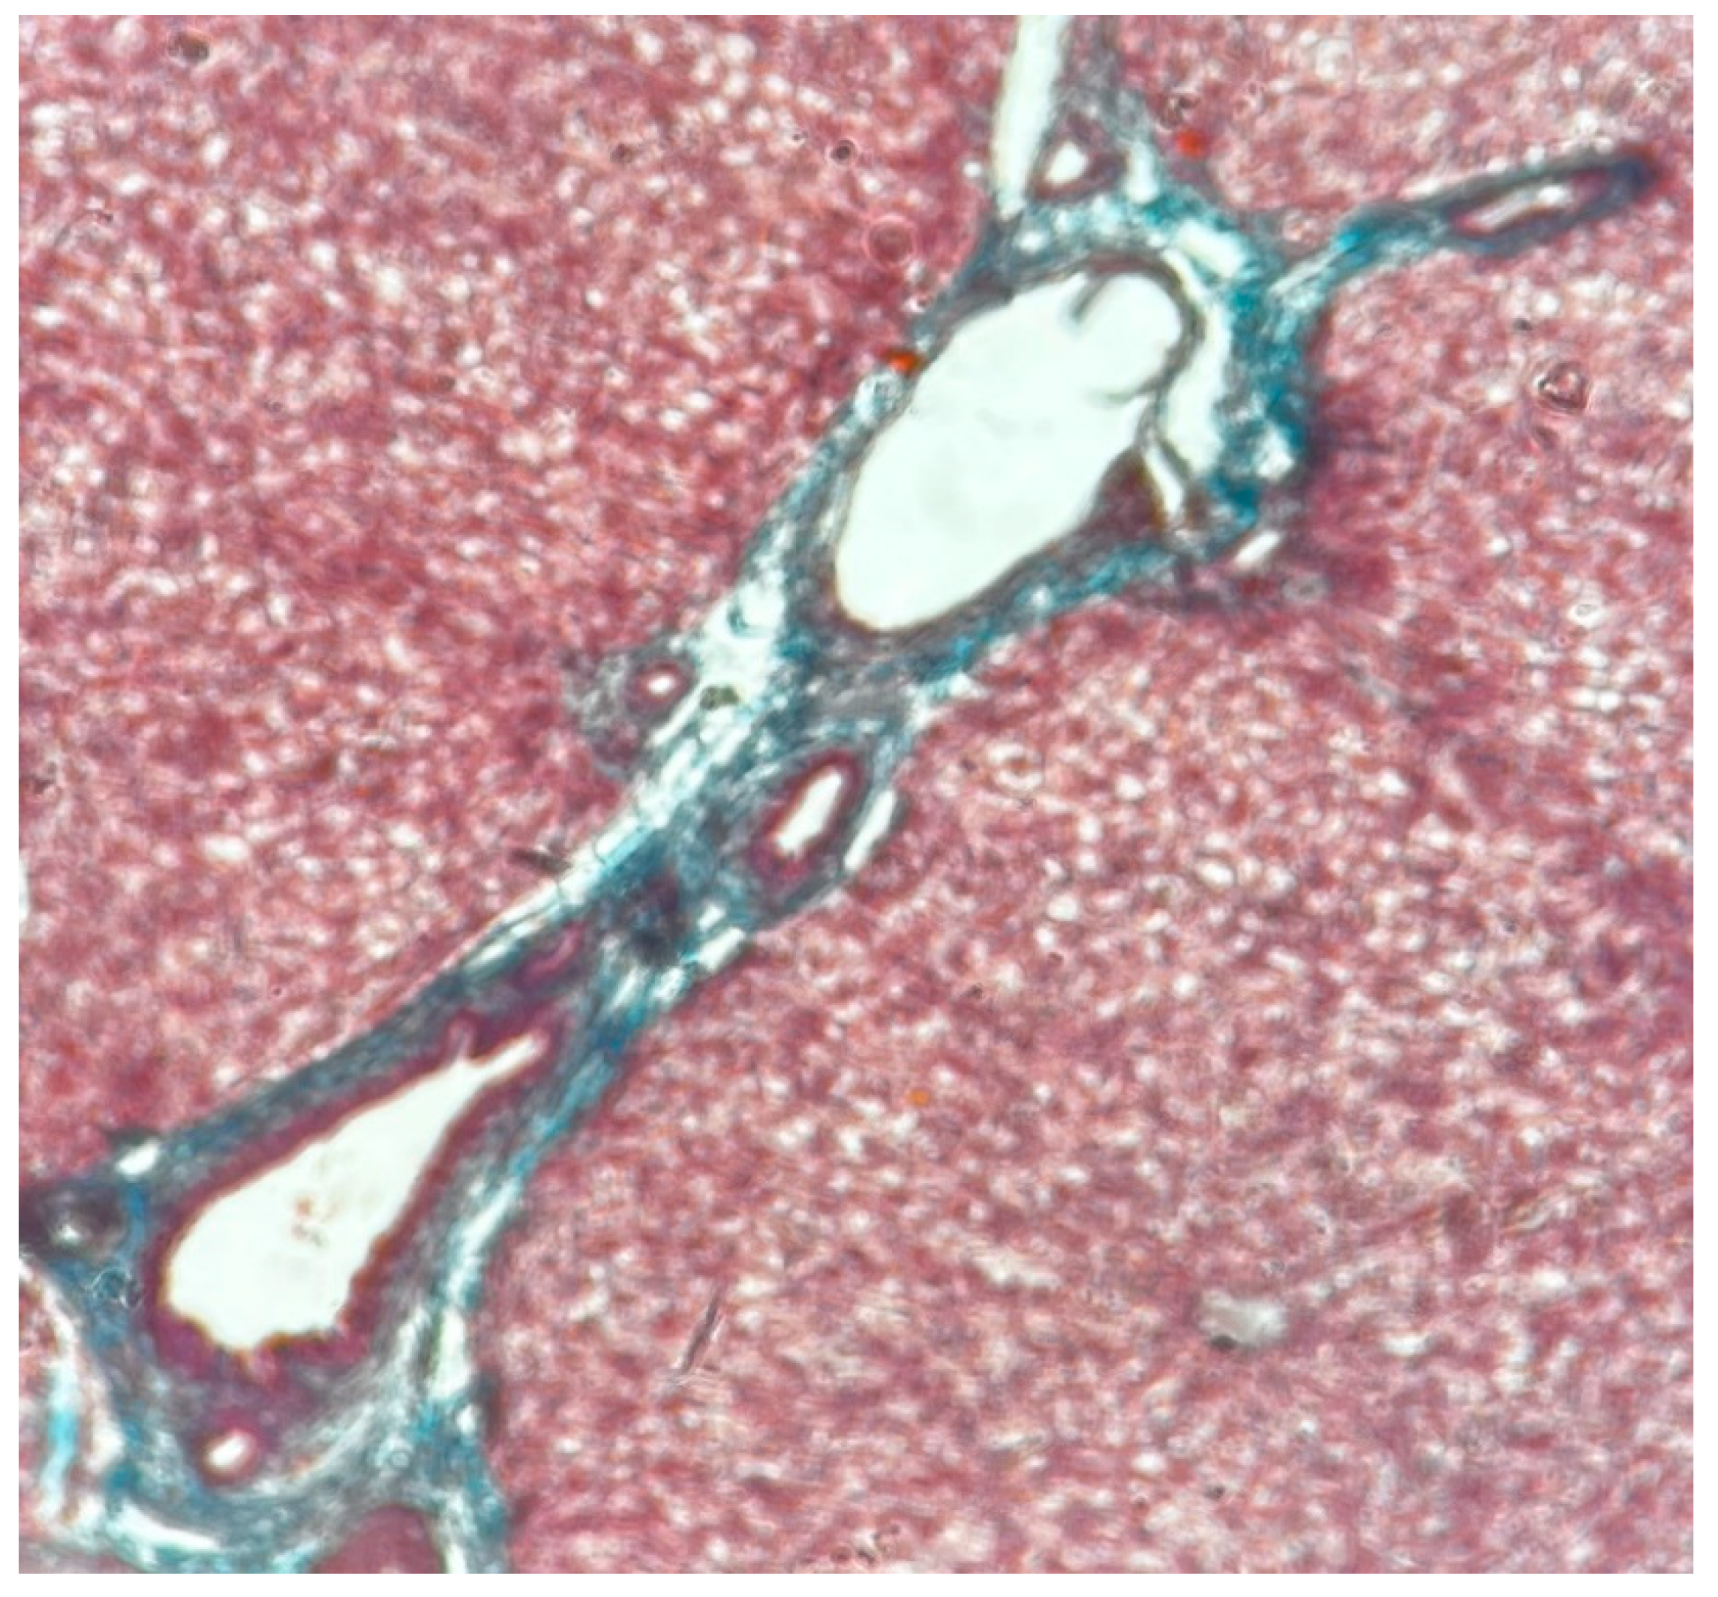

The functional unit of the liver is the lobule with hexagonal form. Kienann space is specific for liver strucutre, including a portal triad (portal vein, hepatic artery, bile duct) sits at each corner of the hexagon. Mitochondri as points observing with lens x40. Portal vein with enlarge lumen (Figure 1).

Also Kiernann space, hepatocytes, connective septa, in normal liver(Figure 2).

Figure 2. Normal liver x10 Goldner Szekely stain.